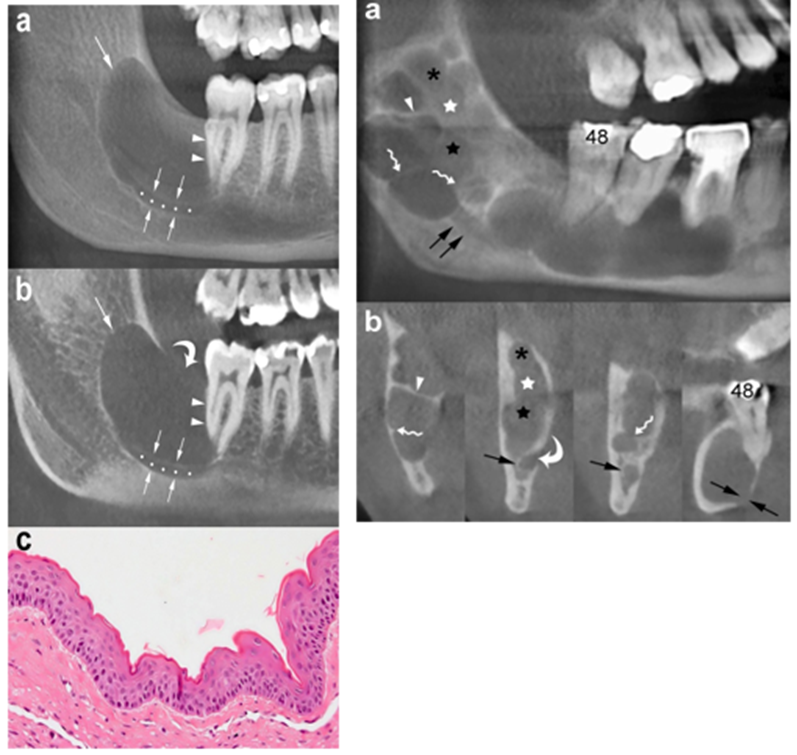

Radiographically, OKCs appear as a well-defined unilocular or multilocular radiolucency bounded by corticated margins (Figure. 1). Unilocular lesions are predominant, whereas the multilocular variant is observed in approximately 30% of cases, most commonly in the mandible (Figure. 1b) [9, 29]. On panoramic radiography, mandibular unilocular OKCs may show few and incomplete septa within the lesions; this finding is more common in larger than in smaller OKCs (Figure. 2).

Mandibular OKC. Panoramic (a) and cross-sectional (b) cone beam computed tomography (CBCT) images display an osteolytic odontogenic lesion in the posterior left mandible and ramus, with a growth predominantly along the length of the bone (double-headed arrow) and minimal expansion of the buccal and lingual cortices (curved arrows). Note mesial displacement of the impacted third molar (38) and inferior displacement of the mandibular canal (arrowheads and dots). Small and incomplete internal septum (small black arrows) due to the endosteal scalloping of the cortical plate are also shown. Wavy arrow, mandibular foramen

The difference between the growth pattern of mandibular and maxillary OKCs may be partly due to the higher cortical thickness of the mandible compared to that of the maxilla [15]. On CT images, OKCs typically manifest as osteolytic lesions that exhibit a unilocular (Figures. 9 and 10) or a predominantly unilocular morphology with few and incomplete septa (Figures. 7 and 8). The multilocular presentation with adjacent satellite cysts (daughter cysts) is possible, particularly in large lesions (Figure. 11). In these cases, loculations are usually large and few (soap-bubble appearance)

Panoramic CBCT images with 20-mm (a) and 0.5-mm (b) slice thickness of an OKC show a unilocular lesion with well-defined and corticated margins located in the posterior sextant and ramus of the right mandible (arrows), near the distal root of the second molar (arrowheads). Note the interruption of the superior border of the retromolar region (curved arrow) and inferior displacement of the mandibular canal (opposing arrows and dots). c Histological image shows the typical parakeratinised stratified squamous epithelial lining with corrugated surfaces (H-E 10×)

Panoramic CBCT image with 20-mm slice thickness (a) shows a multilocular OKC. On this reconstruction, septa seem to divide the lesion into multiple loculations. Cross-sectional CBCT images reconstructed as 0.5-mm-thick sections (b) demonstrate that some of these septa are complete (arrowheads) and some are incomplete (wavy arrows). Note that certain small loculations shown by the panoramic CBCT image (black asterisk, white and black stars) actually correspond to a single large loculation with scalloped borders. Compression and lingual displacement of the mandibular canal, deep to the root of the third molar (48), is also shown (opposing arrows). Curved arrow, mandibular foramen; arrows, mandibular canal